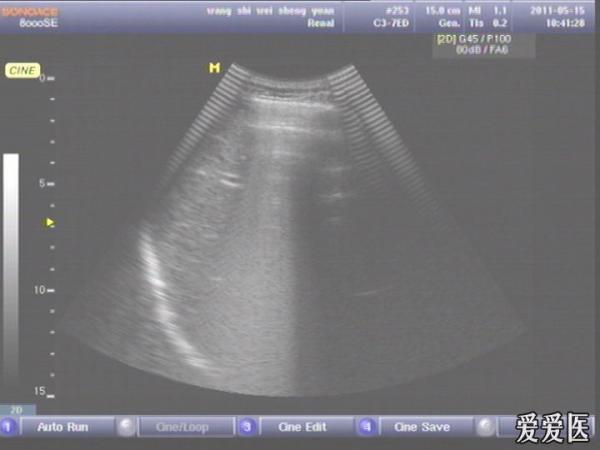

患者,男,38岁,进食后突发上腹部持续性剧烈疼痛一小时来查。超声见横膈与肝之间、上腹部皮下气体强反射回声,后伴多重反射,肝前、肝肾间隙,腹腔肠管间均可见游离无回声区。直视腹部见上腹部似板样。结合病史提示“胃肠道穿孔”。急诊手术证实。